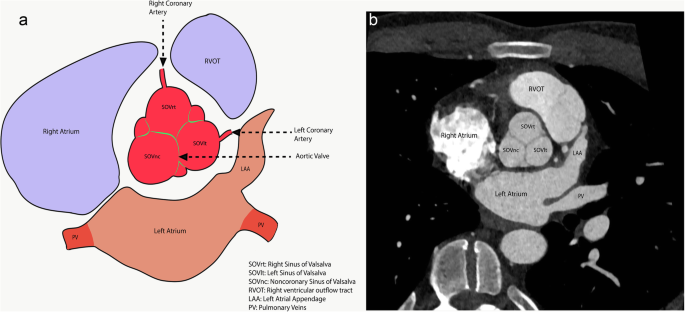

The left ventricle outflow tract (LVOT) continues into the systemic circulation as thoracic aorta. The aortic root is the bridge between the LVOT and the ascending aorta. Aortic root is the proximal-most segment of the aorta from the aortic annulus to the sinotubular junction. In surgical literature, the aortic annulus is described as the plane of attachment of aortic cusps with the aortic wall [19]. In radiology and cardiology literature, the aortic annulus is described as the nadir of the attachment of the aortic leaflets. Components of the aortic root include the aortic annulus, aortic leaflets with their attachments and trigones, the sinuses of Valsalva (SOV), and the sinotubular junction (STJ) (Fig. 2). The three leaflets form the aortic valve and provide its main sealing mechanism [20]. In healthy individuals, the aortic root is directly anterior to the left atrium with no soft tissue in between (Fig. 3). SOV are the three bulges in the aortic root, between the valve and the sinotubular junction (Fig. 2). SOV are named based on the coronary origin. The anterior bulge from which the right coronary artery normally originates is the right SOV, and the left posterior bulge from which the left coronary artery normally originates is the left SOV. The right posterior bulge which faces the interatrial septum and has no coronary artery origin is called the non-coronary SOV. The illustrative and CTA anatomy of the SOV is highlighted in Fig. 4. The ascending aorta is the part of the aorta between the sinotubular junction and the origin of the first arch vessel. Normally, the proximal aorta lies posterior and to the right of the pulmonary artery.